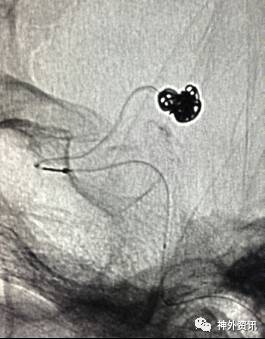

大C塑形

10mm以上的大动脉瘤:

(1)C型头端完全进入动脉瘤囊内,微导管的盘旋有利于均匀填塞

(2)避免微导管头端过早踢出

病例一